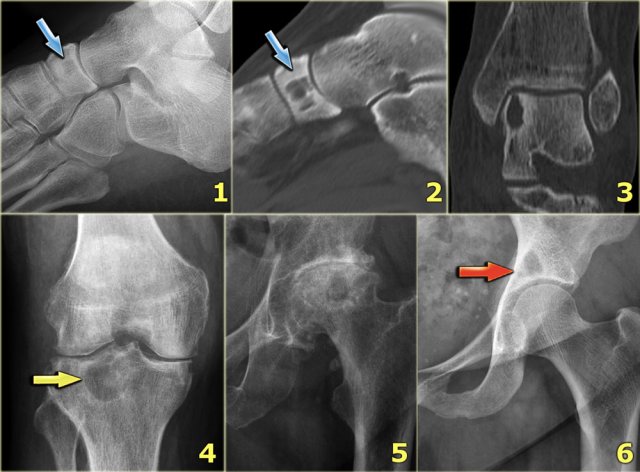

Chondroblastoma (6)

Edema is almost always present in chondroblastoma.

Here some examples:

1. Typical chondroblastoma with epiphyseal localization. Some reactive sclerosis and abundant perilesional edema on T2-weighted image with fat saturation.

2. Coronal T2-weighted image with fat saturation demonstratesa chondroblastoma in the femur epiphysis with perilesional edema (same case as above).

3. Sagittal T1-weighted MR image of a lytic lesion with peripheral sclerotic rim in the posterior talar bone in a young patient.

The lesion is hypointense, well-defined with a low intensity rim.

The bone marrow has a low signal intensity due to extensive edema (arrow).

Chondroblastoma (7)

The images show a chondroblastoma in the patella.

Notice the extensive edema (blue arrow)